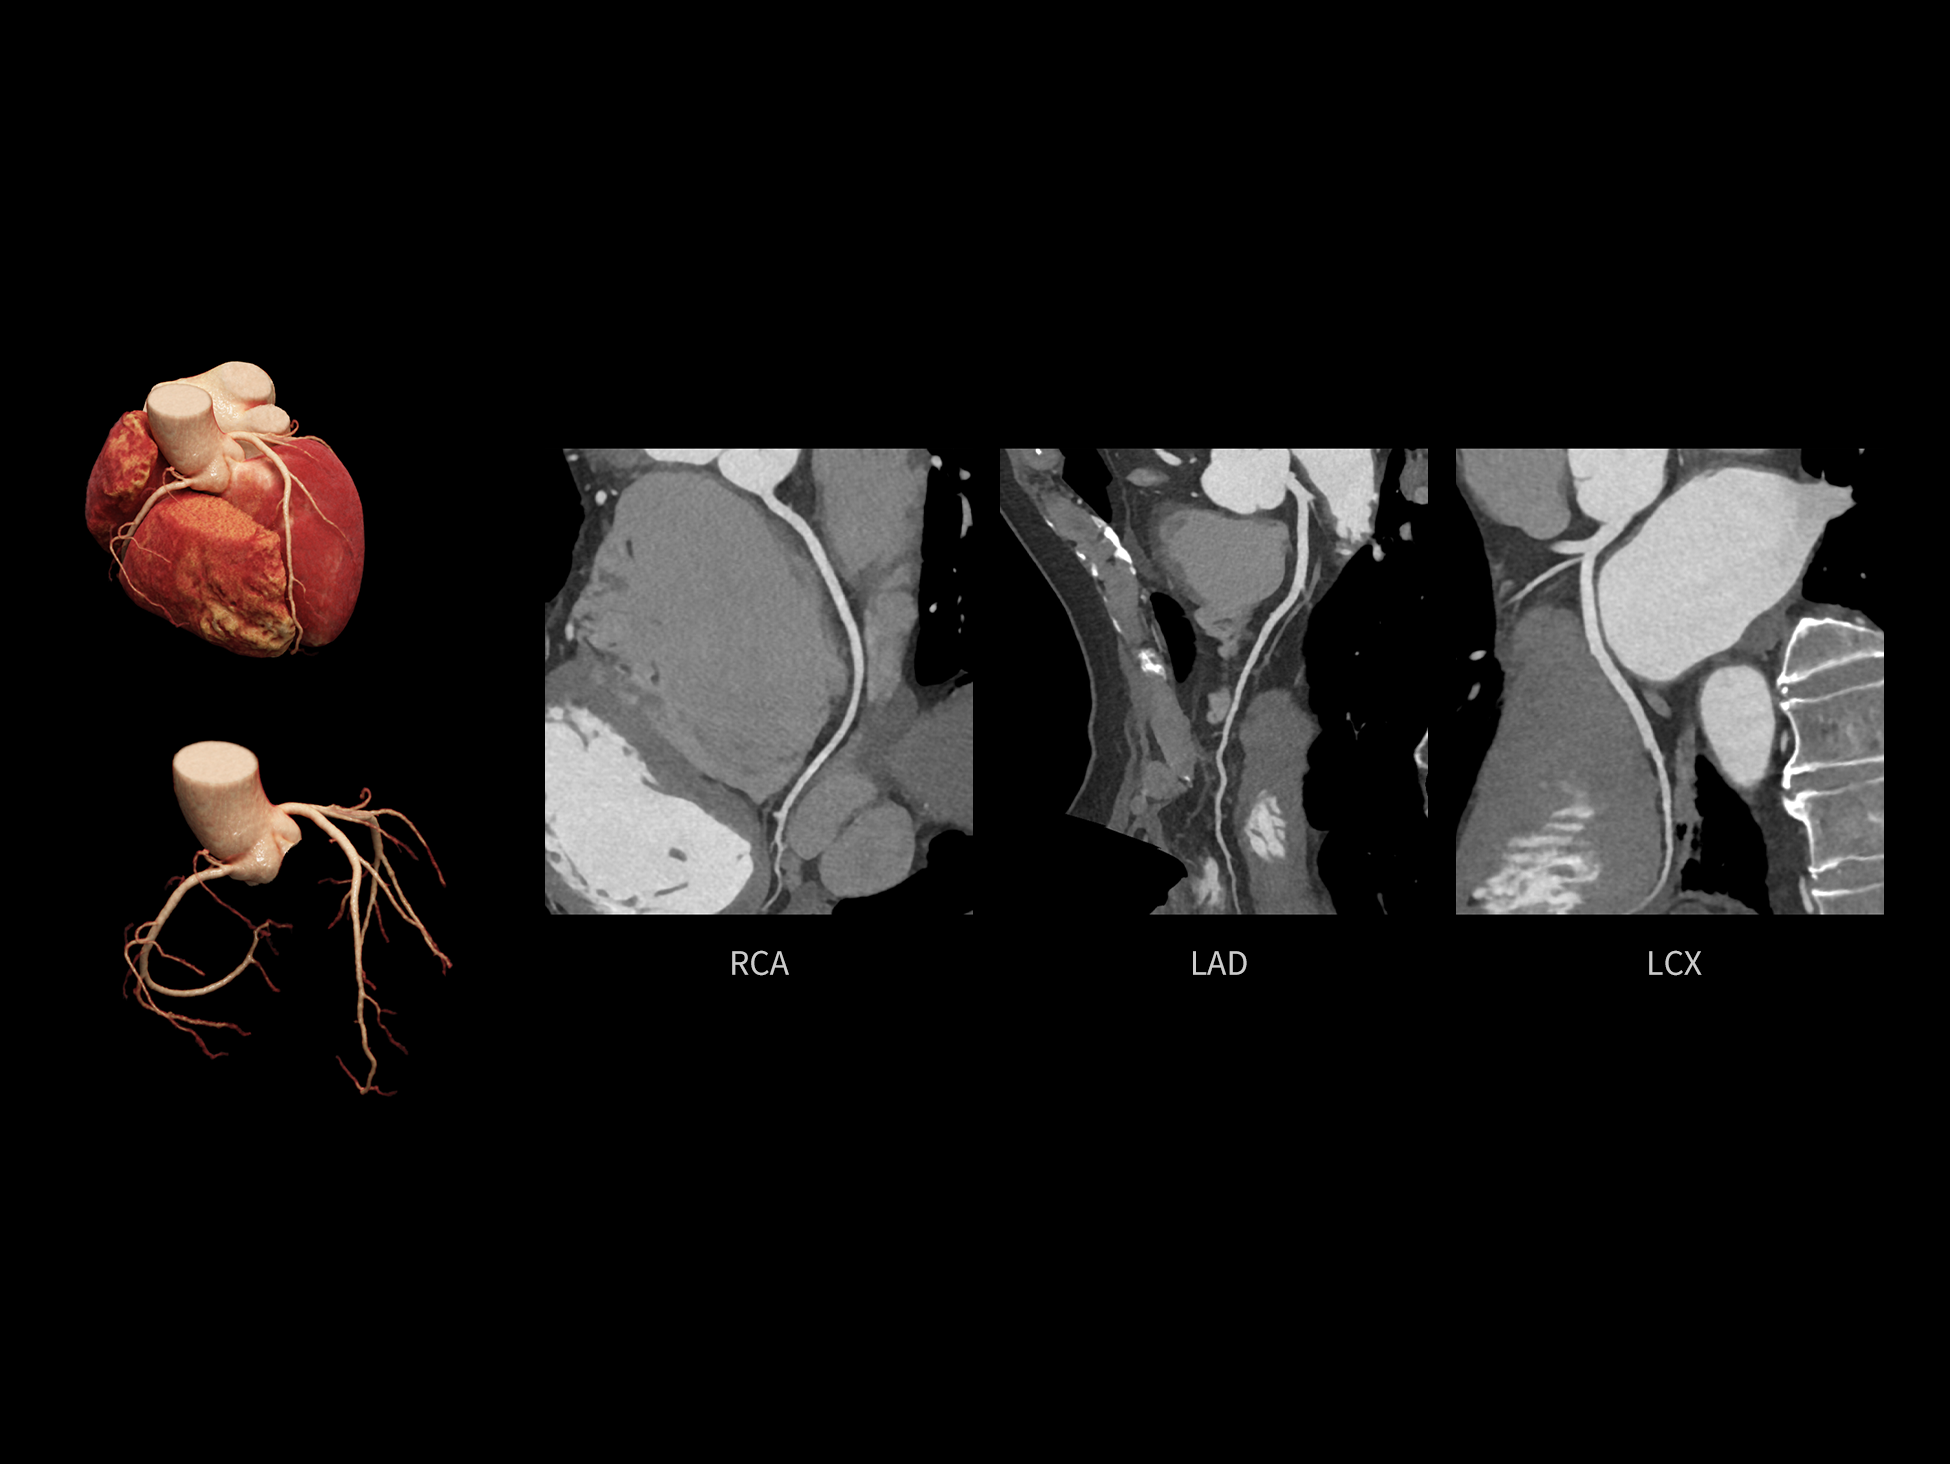

全心结构运动校正

CardioCapture 2.0 可对心肌、瓣膜及心室等结构进行同步运动校正。基于深度学习的心脏精细分割,实现了更完整的心脏全局信息提取,能有效抑制全心运动伪影,显著提升心脏细节的清晰度与诊断可靠性。